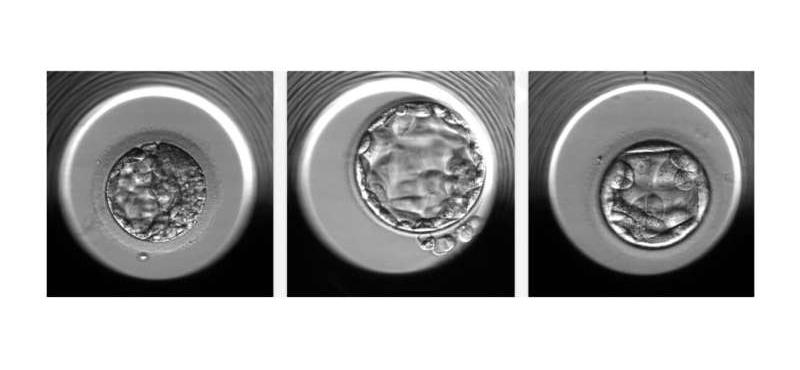

通过STORK-A算法评估的胚胎示例。从左到右,预测的胚胎染色体计数正常或单个染色体异常;预计染色体计数正常的胚胎;

一个胚胎预计有不止一条染色体异常。图片来源:美国康奈尔大学医学院

新算法STORK-A使用受精后5天拍摄的胚胎显微镜图像、胚胎质量评分、母亲年龄等信息,会自动“学习”将数据的某些特征与非整倍体的可能性相关联。研究团队在10378个胚泡的数据集上训练了STORK-A,这些胚泡的倍性状态已知。他们在独立数据集上测试了该算法,发现了相当的准确性结果,证明了STORK-A的普遍性。